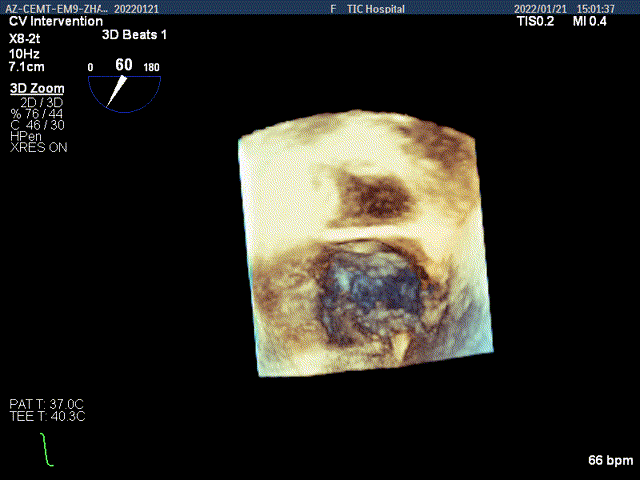

3D MV View:P2区脱垂,宽16.3mm,P3区瓣叶膨隆,与前叶对合不良

TEE Bicom view:二尖瓣后叶P2区脱垂,宽16.3mm

3D视图下调整夹子位置及Rotate

3D视图下夹子对准最大反流束进入左室